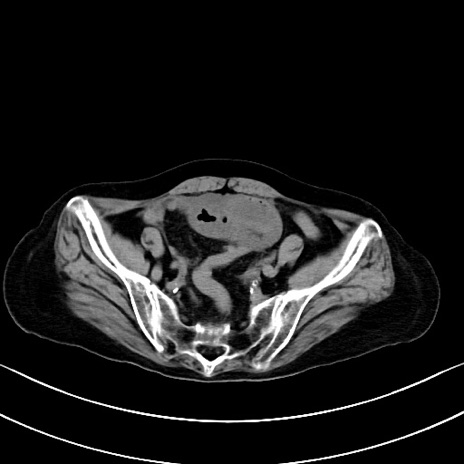

症例40(横断像)他院1日前

横断像